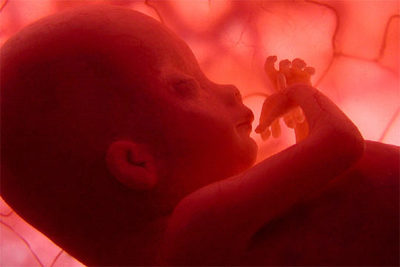

Ya en el último trimestre del embarazo, el escáner enseña la habilidad del feto para percibir sonidos, que le llegan a través de los fluidos corporales, y sus primeras reacciones dormido. El reportaje también se ocupa de embarazos complicados, como el caso de un feto de 26 semanas que es operado en el útero para corregirle una malformación de la cavidad del diafragma, que podría ocasionarle graves daños en el desarrollo de sus pulmones y muy poco margen de supervivencia tras el nacimiento.

Esta operación se filmó íntegramente para el documental gracias a la introducción de una minicámara de alta definición en el abdomen de la madre. Hasta la fecha, los documentales sobre un feto en proceso de gestación eran imágenes en dos dimensiones y en blanco y negro, según el canal dedicado a la naturaleza y a la Ciencia, quién ha informado también que esta producción televisiva se estrenará el próximo 1 de mayo, con motivo de la celebración del Día de la Madre.